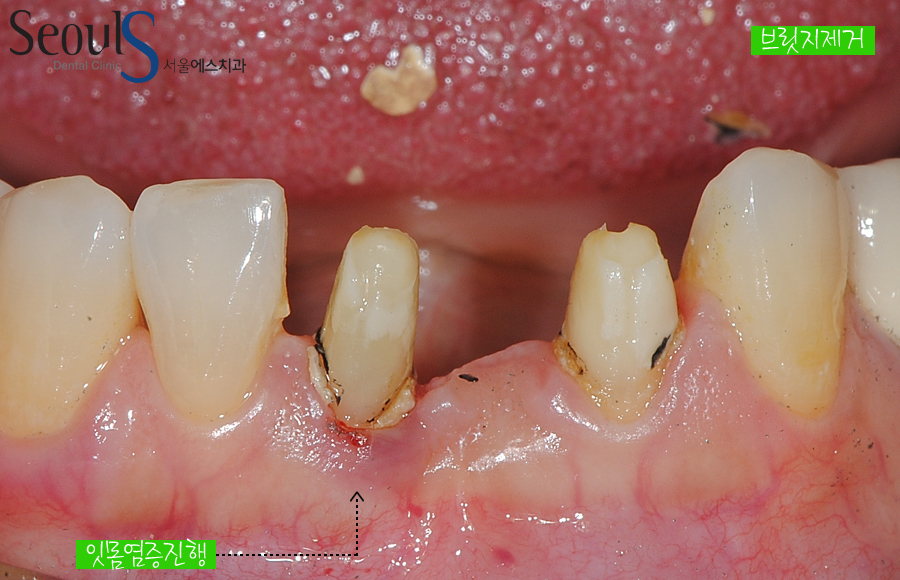

{브릿지 잇몸 염증 때문에 교체}

아래 앞니를 오래전에 브릿지로 치료받았습니다

잇몸 염증이 진행되고 있는 모습입니다

브릿지에 잇몸이 눌려 숨을 쉬지 못해 염증이 진행되고 있습니다

보철물로 치료받은 분들 중…. 잇몸 염증 때문에 고민인 분들이 많을거라 생각됩니다